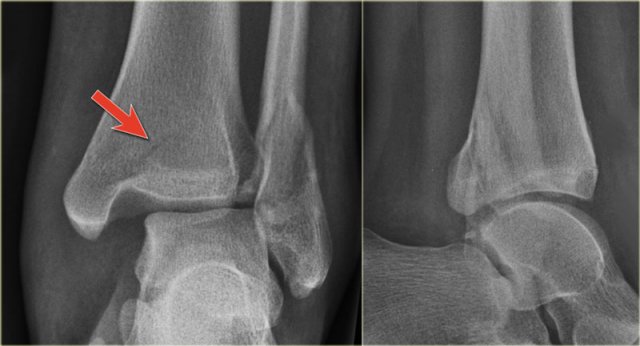

Example 2

• First impression

There is a fracture of the posterior malleolus.

Classification according to Weber is not possible.

An isolated fracture of the posterior malleolus is uncommon, but as part of a supination exorotation (Weber B) or pronation exorotation injury (Weber C) it is quite common.

So we have to re-examine the films to look for signs of a Weber B or C fracture.

• Re-examination

No sign of an oblique fracture of the lateral malleolus, so we can exclude a Weber B fracture.

There is still the possibility of a Weber C fracture, i.e. medial rupture or avulsion, high fibular fracture and finally a posterior malleolar fracture.

Now we notice the subtle avulsion of the medial malleolus (red arrow).

Additional radiographs of the lower extremity demonstrate a high fibular fracture (blue arrow).

• Final report

Weber C stage 4.